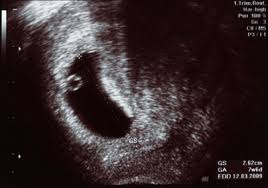

Drei Ultraschall-Untersuchungen sind im Rahmen der Mutterschaftsrichtlinien während der Schwangerschaft vorgesehen. Ultraschall bei 53 erfahrungen. SSW hat der Embryo noch nicht mal die Größe von 1 mm erreicht.

In der ersten und zweiten Woche ist die Frau daher noch nicht schwanger. Ein weiteres Ultraschallbild vom 3. Spätestens dann ist klar.

SSW auf dem Ultraschall zu erkennen ist In der 3. Schwangerschaftswoche Noch 244 Tage bis zur Geburt.